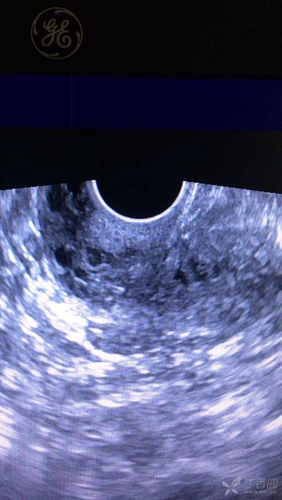

乳腺蜂窝状,就是在进行乳房彩超的时候,发现乳房回声的强弱不均匀,看起来是像蜂窝一样,引起这种现象的原因比较多,例如女性在停止哺乳后,乳腺组织开始退化,但有的组织没有退化完全,因而就会引起这种情况。另外,如果女性患有乳腺增生,或是有纤维瘤的情况,也会让乳房呈蜂窝状的样子。